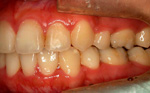

●主 訴 ― 下口唇の突出と叢生

●治療期間 ― 約7.5ヶ月

●治療内容 ― FLB舌側矯正装置、及びヘミオステオトミーによるスピード矯正(抜歯ケース) |